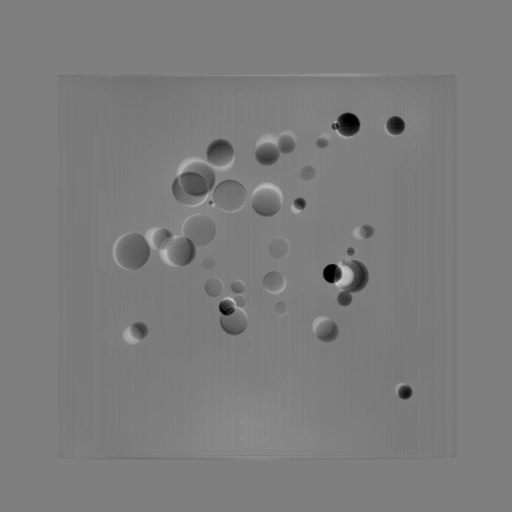

Refer to caption

(a) 3D bead phantom

(b) Perspective 0superscript00^{\circ}

(c) Perspective 90superscript9090^{\circ}

(d) 0superscript00^{\circ} and 90superscript9090^{\circ}

(e) 0superscript00^{\circ} and 90superscript9090^{\circ} OPBP

Figure 5: Perspective projection images from two orthogonal views for a 3D bead phantom as an example: (a) a 3D bead phantom where the background cylinder is omitted for better visualization of the beads; (b) the perspective projection of the 3D bead phantom from the 0superscript00^{\circ} view; (c) the perspective projection of the 3D bead phantom from the 90superscript9090^{\circ} view; (d) the RGB stack of the 0superscript00^{\circ} and 90superscript9090^{\circ} perspective projection images; (e) the RGB stack of the 0superscript00^{\circ} and 90superscript9090^{\circ} OPBP images. The intensity range [0, 11] in projection images is converted to [0, 255] for visualization.

As an illustrative example, the two perspective projection images from two orthogonal views for a 3D bead phantom are displayed in Fig. 5. To better compare the perspective projection images from the two orthogonal views, an RGB image is formed in Fig. 5(d), where the red and blue channels use images from the 0superscript00^{\circ} perspective view, while the green channel uses images from the 90superscript9090^{\circ} perspective view. Here we fill up three channels so that pixels, which have similar intensity from both views, appear grey such as the background cylinder area. In the formed RGB image, the magenta beads from the 0superscript00^{\circ} view and the green beads from 90superscript9090^{\circ} view are located in different positions. Similarly, an RGB image consisting of the 0superscript00^{\circ} perspective projection image (red and blue channels) and the 90superscript9090^{\circ} OPBP image (green channel) is displayed in Fig. 5(e). In Fig. 5(d) the bead-to-bead (or point-to-point) correspondence between two views is not straightforward because of the large number of beads. It is the same for the bead-to-stripe (point-to-line) correspondence in Fig. 5(e). Therefore, it is challenging for neural networks to learn perspective deformation from two orthogonal views.